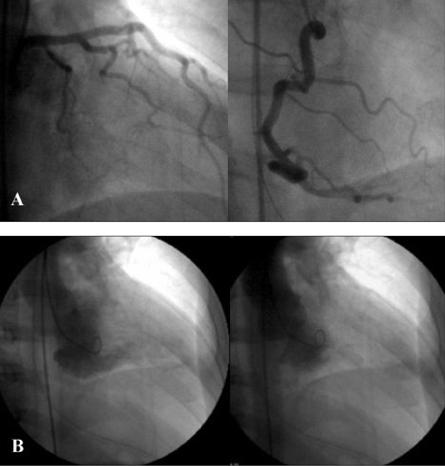

Mid-ventricular obstructive hypertrophic cardiomyopathy (MVOHCM) is a rare type of cardiomyopathy, associated with apical aneurysm formation in some cases. We report a patient presenting with ventricular fibrillation, an ECG with an above normal ST segment, and elevated levels of cardiac enzymes but normal coronary arteries. Left ventriculography revealed a left ventricular obstruction without apical aneurysm. There was a significant pressure gradient between the apical and basal sites of the left ventricle. Cine magnetic resonance imaging (MRI), performed on the 10th hospital day, showed asymmetric septal hypertrophy, mid-ventricular obstruction, and an apical aneurysm with a thrombus. The first evaluation by contrast-enhanced imaging showed a subendocardial perfusion defect and delayed enhancement. It was speculated that the intraventricular pressure gradient, due to mid- ventricular obstruction, triggered myocardial infarction, which subsequently resulted in apical aneurysm formation.

心室中部梗阻性肥厚型心肌病(MVOHCM)是一种罕见的心肌病类型,部分病例与心尖部动脉瘤形成有关。我们报告一例患者,表现为心室颤动、ST段高于正常的心电图以及心肌酶水平升高,但冠状动脉正常。左心室造影显示左心室梗阻但无心尖部动脉瘤。左心室心尖部和基部之间存在显著的压力梯度。在住院第10天行电影磁共振成像(MRI)检查,显示室间隔不对称肥厚、心室中部梗阻以及伴有血栓的心尖部动脉瘤。首次对比增强成像评估显示心内膜下灌注缺损和延迟强化。推测由于心室中部梗阻导致的室内压力梯度引发心肌梗死,随后导致心尖部动脉瘤形成。